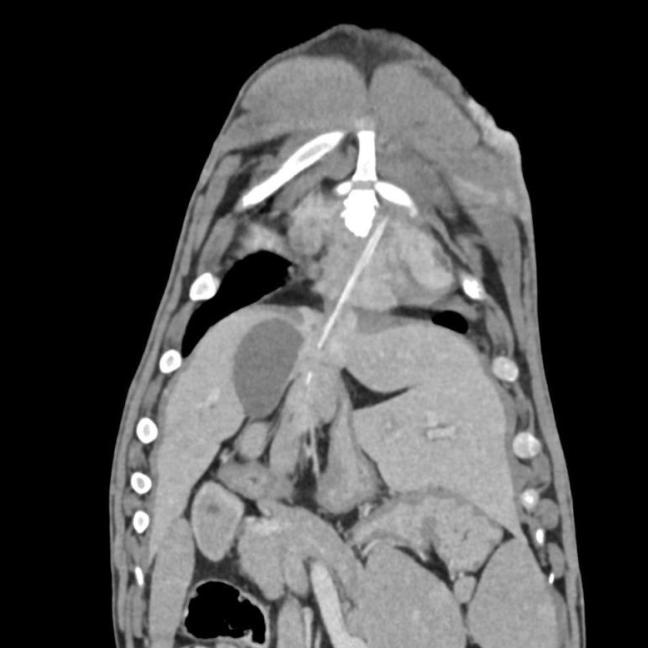

Eazy has recently undergone a CT scan and major thoracic surgery with Melbourne Animal Referral Services to remove a foreign body (a skewer measuring in two parts 8cms and 12cms) This foreign body is believed to have been ingested 3+ years ago when we look back on his medical history taking into account when he first showed some oozing on his midline.